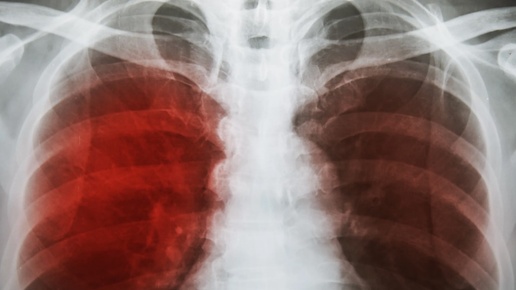

Кашель с кровью, или гемоптизис, — тревожный симптом, который встречается у 5–15% людей с респираторными проблемами и часто ассоциируется с туберкулёзом, заболеванием, поражающим 10 миллионов человек ежегодно, по данным Всемирной организации здравоохранения (ВОЗ). Однако этот симптом может быть признаком более опасных состояний, таких как рак лёгких (2,2 миллиона случаев в год), лёгочная эмболия или бронхоэктатическая болезнь, особенно у людей старше 50 лет, когда риск серьёзных патологий возрастает на 15% каждые 10 лет...

Кашель — сам по себе неприятный симптом. Что делать, если он осложняется кровью? Гемоптизис (кашель с кровью) может быть признаком различных серьезных заболеваний и состояний. Кашель с кровью может сопровождаться другими симптомами, такими как одышка, боль в груди, лихорадка или потеря веса. Это тревожный симптом, который требует незамедлительного обращения к врачу. 1. Инфекции дыхательных путей: — Пневмония. Воспаление легких может вызывать кашель с кровью, особенно если есть повреждение кровеносных сосудов...